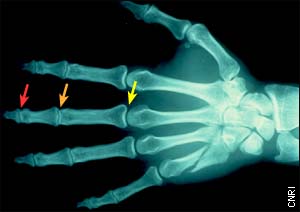

The red arrow denotes the distal interphalangeal (DIP) joint; the orange arrow, the proximal interphalangeal (PIP) joint; and the yellow arrow, the metacarpophalangeal (MCP) joint. Side note: this X-ray image shows a fractured metacarpal bone (below the little finger).

Dr. Scott: Each finger has three bones -- the distal (fingertip), middle, and proximal phalanges -- and, like other joint structures in the body, it's stabilized by ligaments and tendons. When the finger receives a blow to the tip, the ligaments and tendons can be stretched and torn, and one or more of three joints can be injured: the distal interphalangeal (or DIP; the first knuckle), proximal interphalangeal (or PIP; the middle knuckle), and metacarpophalangeal (MCP; the knuckle at the base of the finger).

Probably the most vulnerable area is the PIP joint. One of the reasons it is the most commonly injured area is that it's a little bit more exposed than the other joints and doesn't have much protection around it. The PIP joint also has a very large arc of motion, which means that the range of the joint is huge - it goes from full extension or zero degrees to perhaps to 110 or 115 degrees of flexion, well past 90. So it's a very high-demand joint and is required for all finger motion - from fine dexterity, like threading a needle, to catching a football.